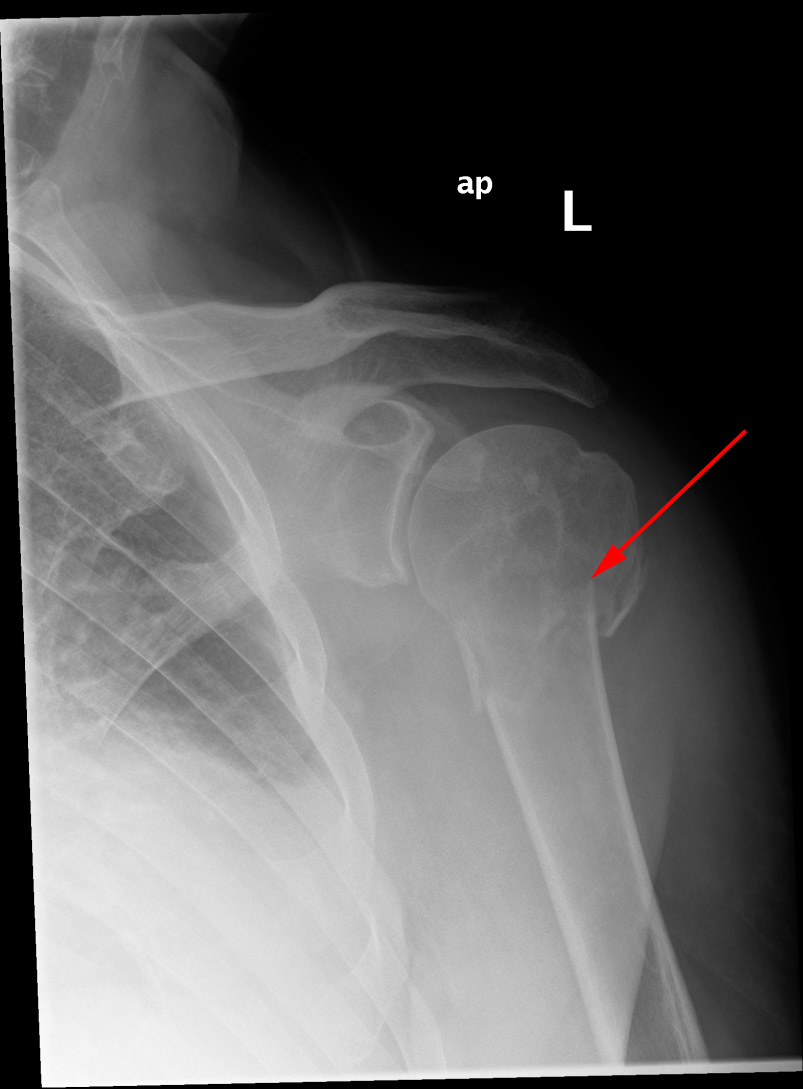

Røntgenundersøgelse af skulderen viser et brud øverst på overarmen (rød pil) – humerusfraktur.